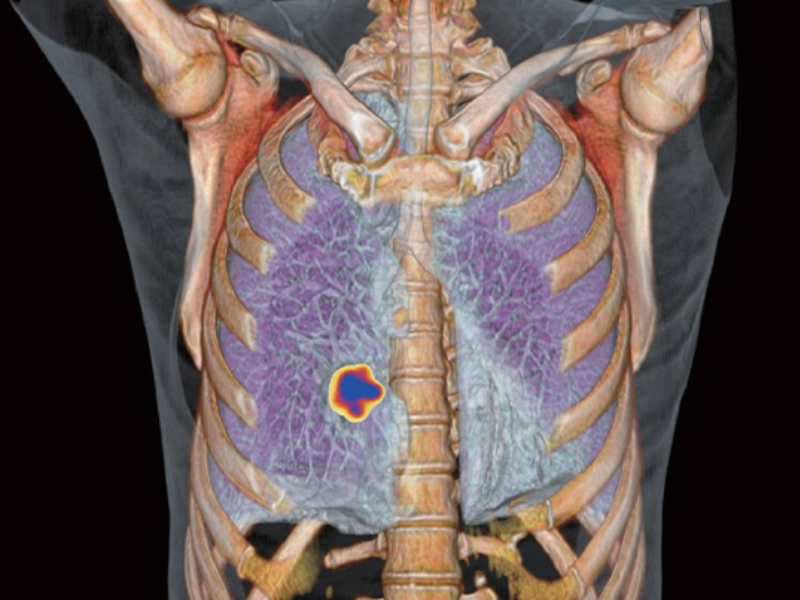

Whole Organ Coverage